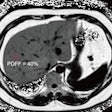

Examples of false-positive findings: Contrast-enhancement in the T1 Dixon water-only image of the pharyngeal wall (white arrow in a) was confirmed as regular hyperplastic pharyngeal tissue on biopsy. A focal contrast-enhancement of the gastric wall (white arrow in b) was no longer detectable on follow-up MRI (c) and was retrospectively deemed an artifact.

Examples of false-positive findings: Contrast-enhancement in the T1 Dixon water-only image of the pharyngeal wall (white arrow in a) was confirmed as regular hyperplastic pharyngeal tissue on biopsy. A focal contrast-enhancement of the gastric wall (white arrow in b) was no longer detectable on follow-up MRI (c) and was retrospectively deemed an artifact.